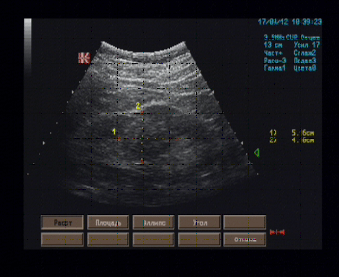

Правая почка 130 х 50 мм, положение и форма типичные, контуры ровные, паренхима толщиной 18 - 19 мм., однородная, равномерно гипоэхогенная, кортико-медуллярная дифференцировка умеренно выражена, ЧЛС не расширена, в среднем сегменте передней стенки со стороны ЧЛС к паренхиме прилежит гипоэхогенное образование неправильной овальной формы размерами 51 х 41 х 40 мм, имеющее неровные контуры, однородное внутреннее строение.

Эхографические признаки солидного образования среднего сегмента правой почки (дифференцировать колонку Бертина от опухоли почечного синуса).